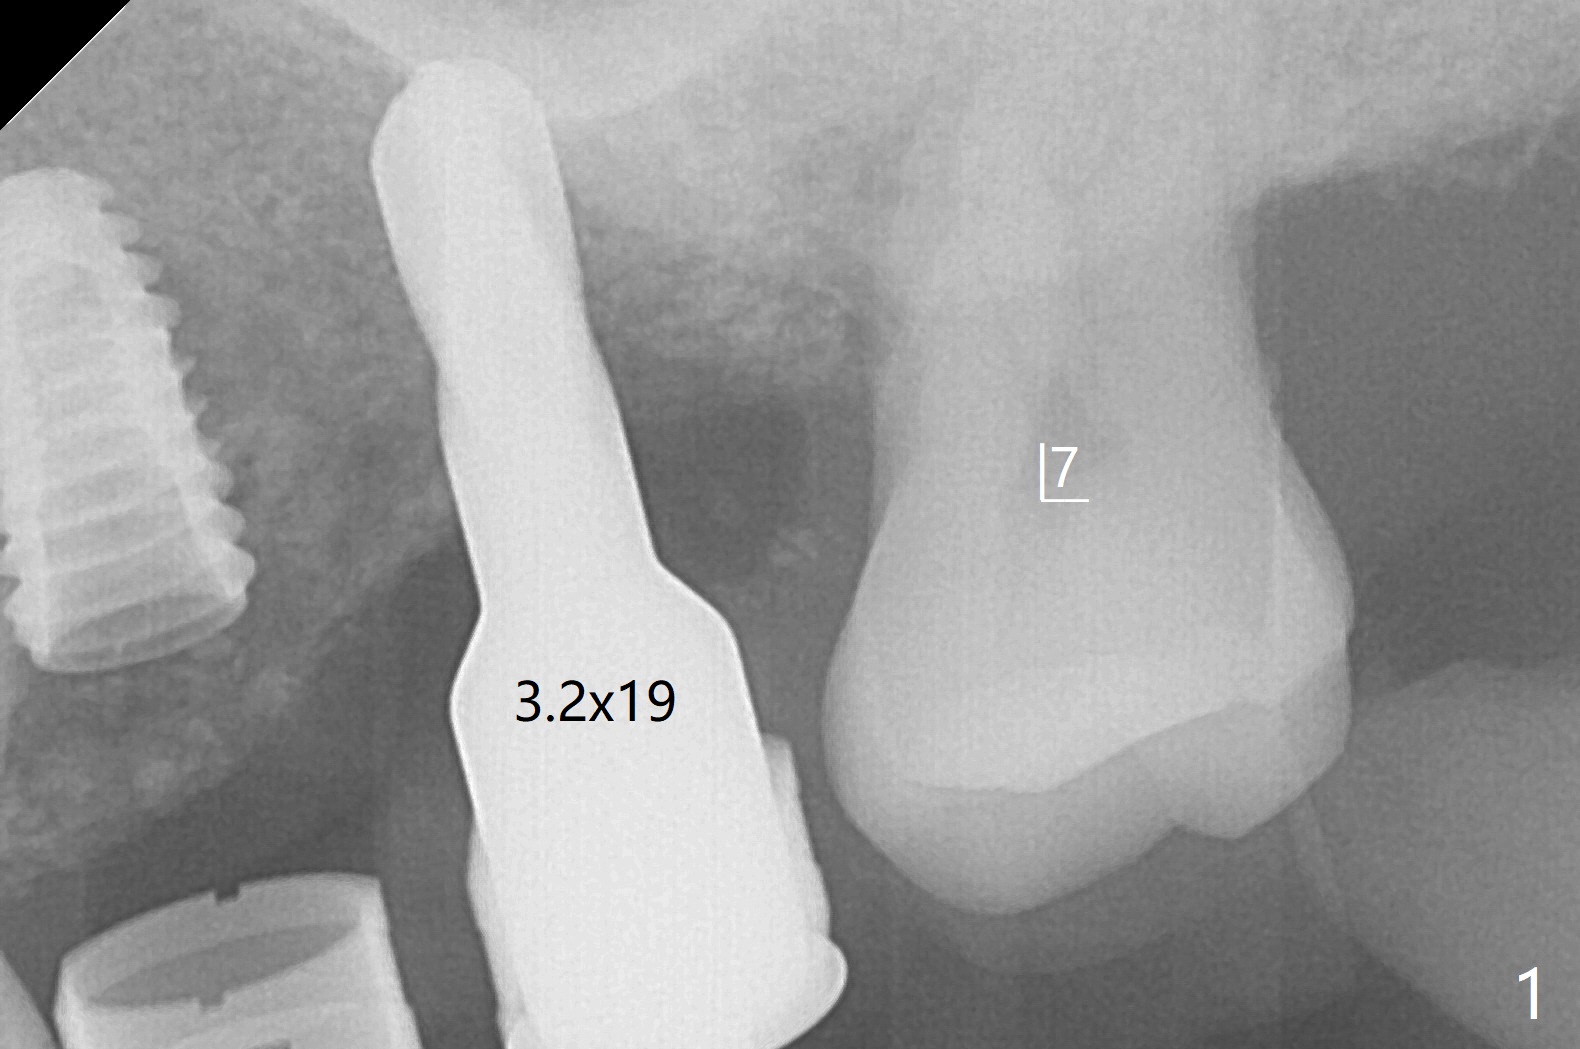

左上六植牙第三次失败后五个月,牙槽嵴宽度尚可,切开后放置导板,3.2乘19毫米园钻头好像接近上颌窦底板(图一),但是粘性骨块和4乘10毫米报废植体就不能进入上颌窦(图二),最后不得不使用3毫米Bicon骨凿,之后同一个报废植体就似乎进入上颌窦(图三),4.5乘8.5毫米正式植体植入深度和稳定性均正常(图四),腭侧植体稍微暴露,放置愈合螺丝后,放置骨粉和PRF膜,缝合,左上5植体放置5.7x4.5(4)毫米基台,固定牙周敷料。术后5.5个月植体好像整合(图五),缺牙间隙特别小,5临时牙冠(P)必须取出才能切开暴露植体,放置5.5x5毫米愈合基台(图六)。伤口愈合后,必须做渐进性负荷,之后做简单局部矫正,推7往远中,6缺失3年,7往近中倾斜移位。两周后牙周敷料脱落,伤口愈合,放置修复基台,故意将基台平面朝远中,足够空间制作临时牙冠(图七)。调整基台长度(比较图七,八)。制作连体牙冠(5,6),有意提高5牙冠高度,使左上7不与对合牙接触,有利于远中移位(图九)。也要在对侧提高咬合(图十)。局部矫正一个月后,磨去右侧咬合垫和磨短左上5,6临时牙冠,前牙还不能完全接触(图十一)。1-2星期前牙开合自行消失,取模做左上5,6牙冠。局部矫正似乎使左上7远中移位大约3毫米(比较图十二,十三)。粘固拧紧后(20 Ncm)14号牙牙冠咬合增高,拍摄根尖片(图十三),两个基台好像仍然完全就位,然后调整咬合。